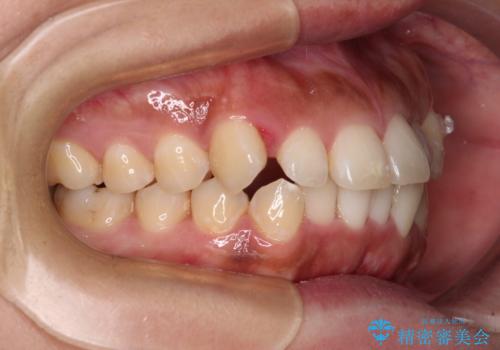

- 前歯の叢生と八重歯を気にして来院された患者様です。

目立たない装置を希望とのことで、インビザラインにて矯正治療を行うこととしました。

インビザライン単体で改善することも可能ですが、八重歯とその後方にある歯列を確実移動させないと、上下正中がずれてしまう可能性があります。

インビザライン単体での治療ではなく、カリエール・ディスタライザーという補助装置を併用して、より確実性を上げることとしました。

補助装置で八重歯を解消しながら、並行してインビザラインで歯列を整えることとしました。